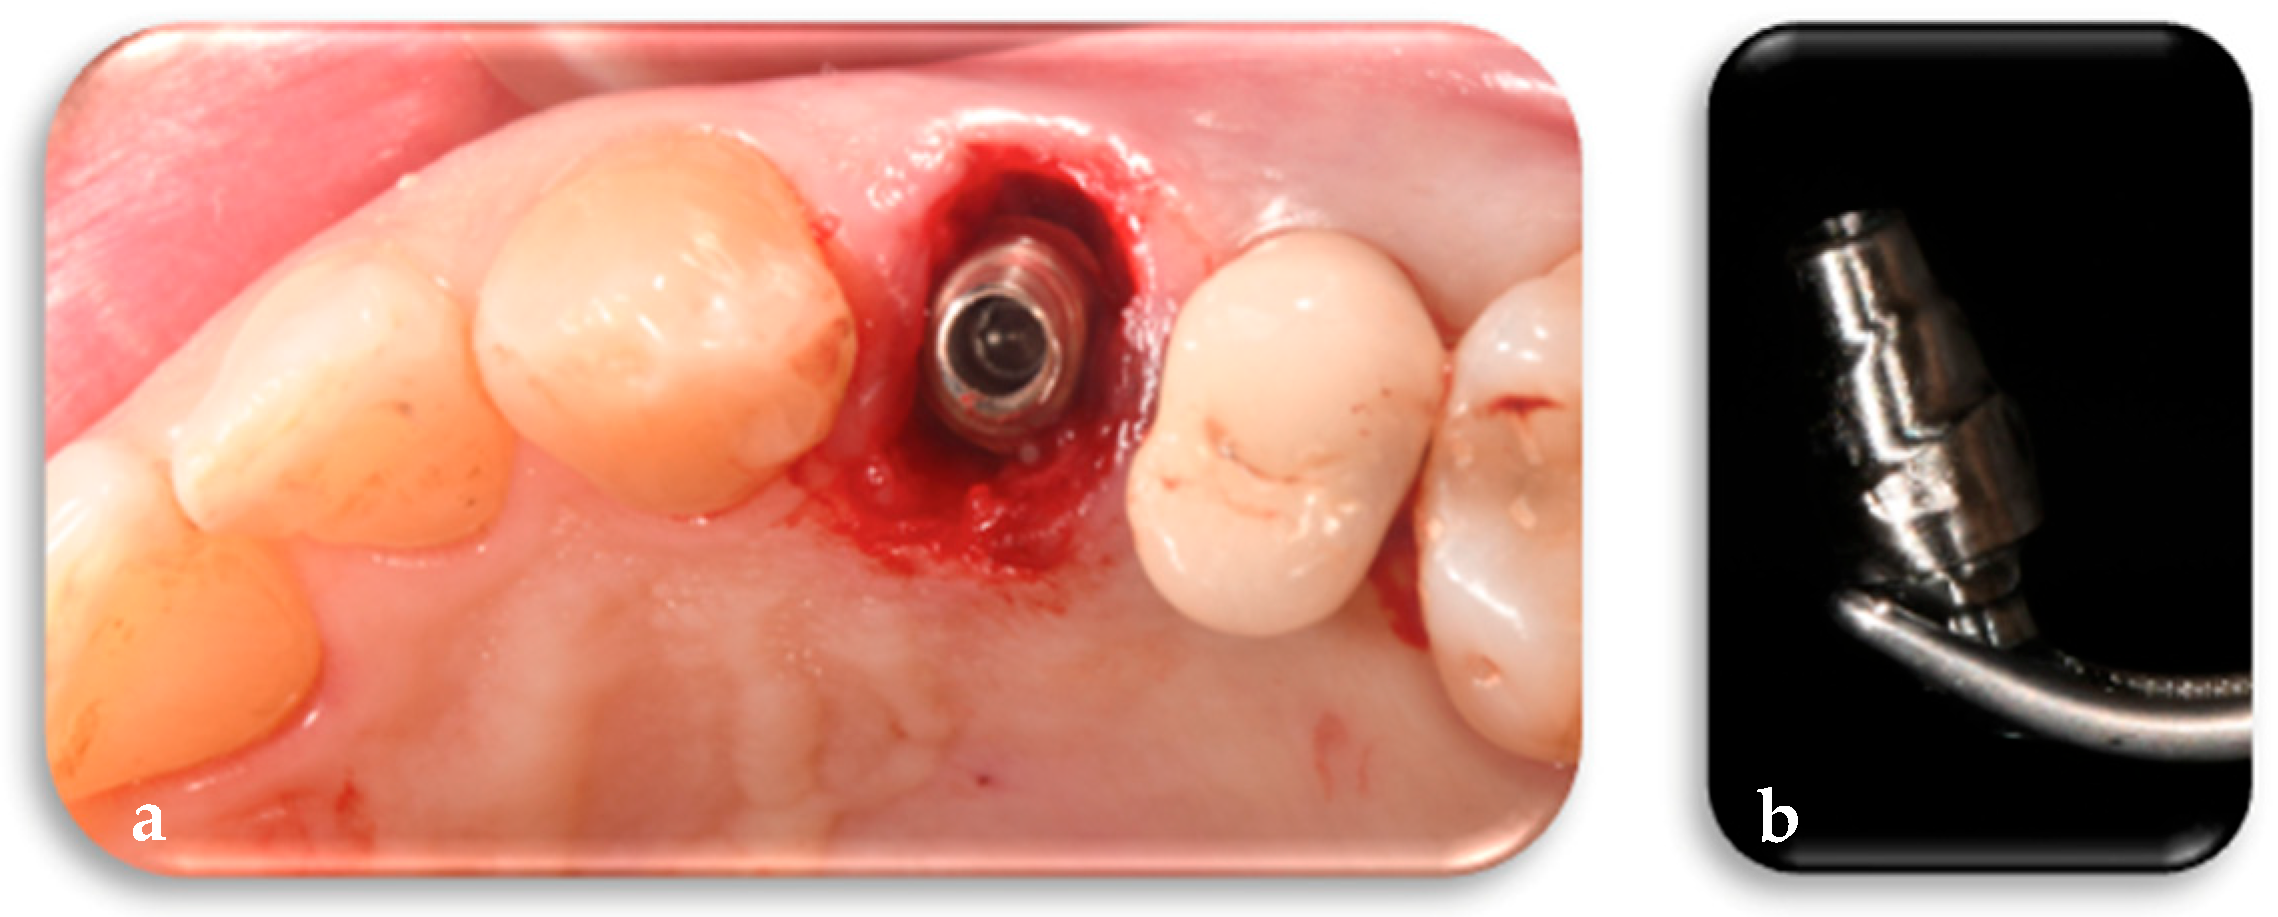

2.1.2. Phase 2: Implant Placement, Delivery of the Definitive Customized Abutment, Coping, Provisional Restoration, and Fitting of the Definitive Framework